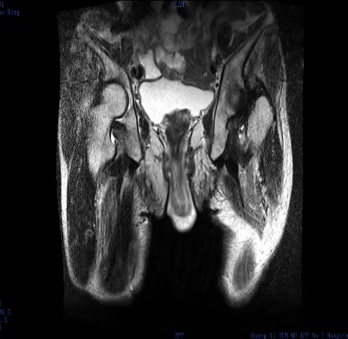

肛肠外科检查发现,周奶奶的肛门处有约 8 cm 脱出肿物,呈「宝塔状」,肛门括约肌明显松弛。结合排粪造影及 MRI 提示,诊断为 III 度直肠脱垂。

「我们发现,虽然周奶奶还有轻度贫血和高血压病史,但整体状况良好,可耐受手术。」肛肠外科团队当机立断决定为周奶奶进行手术治疗,并开展详细术前讨论,为她制定了个体化手术方案:腹腔镜下腹侧补片直肠悬吊固定术(LVMR)。